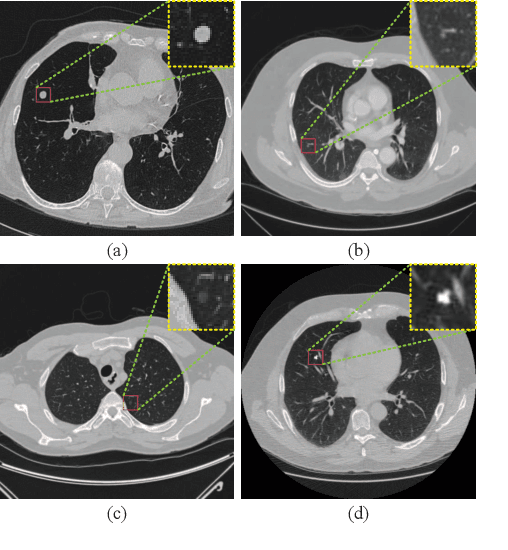

Abstract:Background and Objective:Computer-aided diagnosis (CAD) systems promote diagnosis effectiveness and alleviate pressure of radiologists. A CAD system for lung cancer diagnosis includes nodule candidate detection and nodule malignancy evaluation. Recently, deep learning-based pulmonary nodule detection has reached satisfactory performance ready for clinical application. However, deep learning-based nodule malignancy evaluation depends on heuristic inference from low-dose computed tomography volume to malignant probability, which lacks clinical cognition. Methods:In this paper, we propose a joint radiology analysis and malignancy evaluation network (R2MNet) to evaluate the pulmonary nodule malignancy via radiology characteristics analysis. Radiological features are extracted as channel descriptor to highlight specific regions of the input volume that are critical for nodule malignancy evaluation. In addition, for model explanations, we propose channel-dependent activation mapping to visualize the features and shed light on the decision process of deep neural network. Results:Experimental results on the LIDC-IDRI dataset demonstrate that the proposed method achieved area under curve of 96.27% on nodule radiology analysis and AUC of 97.52% on nodule malignancy evaluation. In addition, explanations of CDAM features proved that the shape and density of nodule regions were two critical factors that influence a nodule to be inferred as malignant, which conforms with the diagnosis cognition of experienced radiologists. Conclusion:Incorporating radiology analysis with nodule malignant evaluation, the network inference process conforms to the diagnostic procedure of radiologists and increases the confidence of evaluation results. Besides, model interpretation with CDAM features shed light on the regions which DNNs focus on when they estimate nodule malignancy probabilities.